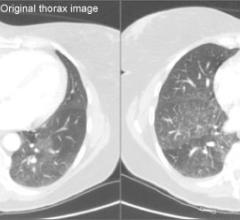

In an effort to lower the radiation doses patients receive from CT scans, Unilabs Röntgen Majorstuen in Oslo, Norway,…